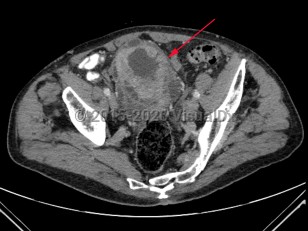

Uterine fibroidsUterine fibroids

Ovarian cancerOvarian cancer

EndometriosisEndometriosis